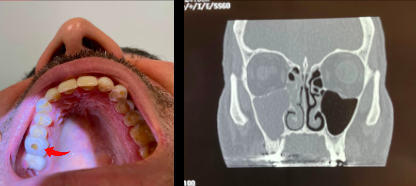

Q

¿Qué se ve en esta imagen?

A

Sinusitis Maxilo-Etmoidal DERECHA

*Las bacterias pueden migrar desde otras lesiones